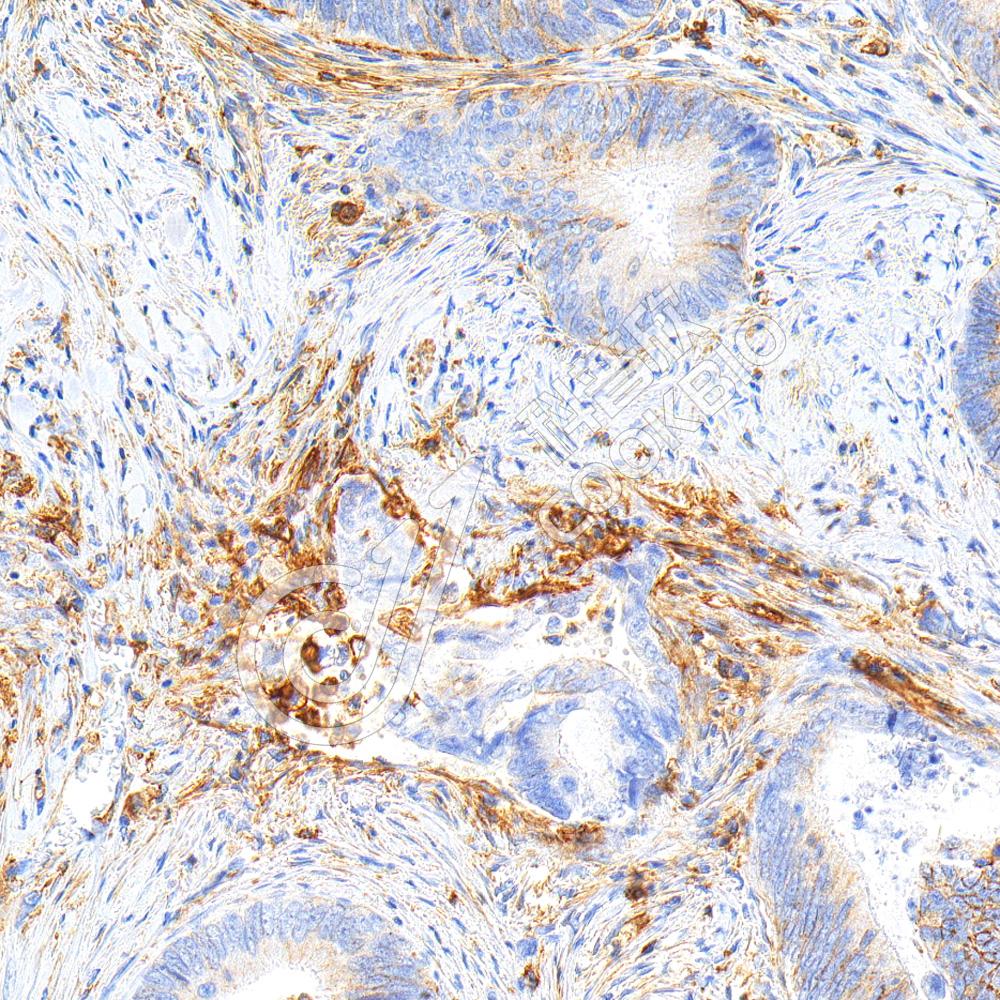

IHC检测Phospho-Tau(S202/T205)蛋白(货号 K5450180).

样品: 大鼠脑, 4%多聚甲醛 (货号KSG1101) 固定12-24小时.

抗原修复: 柠檬酸抗原修复液(干粉, pH 6.0) (KSG1201), 高压锅均匀喷气计时2分钟.

—抗: 1: 300稀释, 4℃ 孵育过夜.

二抗: S-vision免疫组化多聚二抗(山羊抗兔),即用型 (货号KB3906), 室温孵育20分钟.